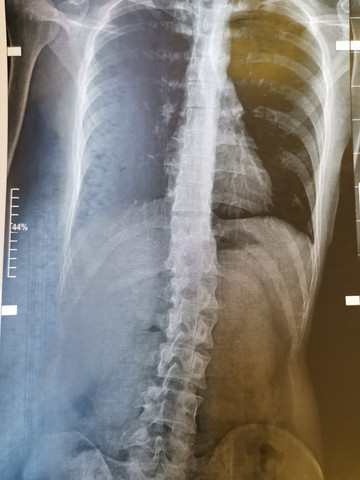

Natürlich soll gleichzeitig auch der Buckel verschwinden und der Patient soll wieder aufrecht durchs Leben gehen können Bevor Sie die Entscheidung für eine Operation treffen, sollten Sie sich eine ExpertenMeinung einholen, denn nur wenige Orthopäden und Wirbelsäulenchirurgen behandeln regelmäßig Skoliosen. Im Oktober 13 wurde bei einer Röntgenaufnahme wegen anhaltender Rückenschmerzen bei mir eine schwere Skoliose diagnostiziert Auf Nachfrage bei der RöKlinik wurde mir dann im Jan 14 eine alte RöAufnahme vom Aug 05 zugeschickt mit der Diagnose LumbalSkoliose LWS. » Einfache Asanas, die Ihnen helfen heilen Skoliose Rückenprobleme sind unangenehm und können nur jene Leiden, die Schrecken verstehen Sie sagen, dass Sie nur so alt, wie die Wirbelsäule sind Und es ist so wahr!.

Rontgen Vorher Nachher Die Gesundheit In Ihren Handen